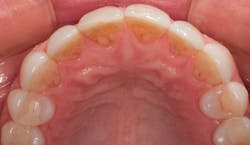

In 2016, she decided that she wanted to replace her veneers with the new bleach-shaded materials available today. In Figure 1, you can see her veneers as they appeared after nineteen years. Note the excellent tissue health and minimal tissue recession. There was a small fracture in the disto-incisal corner of the right central incisor. The incisal view at this date can be seen in Figure 2.

Figure 1: The patient’s porcelain laminate veneers placed in 1997 as seen in 2016

Figure 2: Incisal view of the patient’s porcelain laminate veneers placed in 1997 as seen in 2016